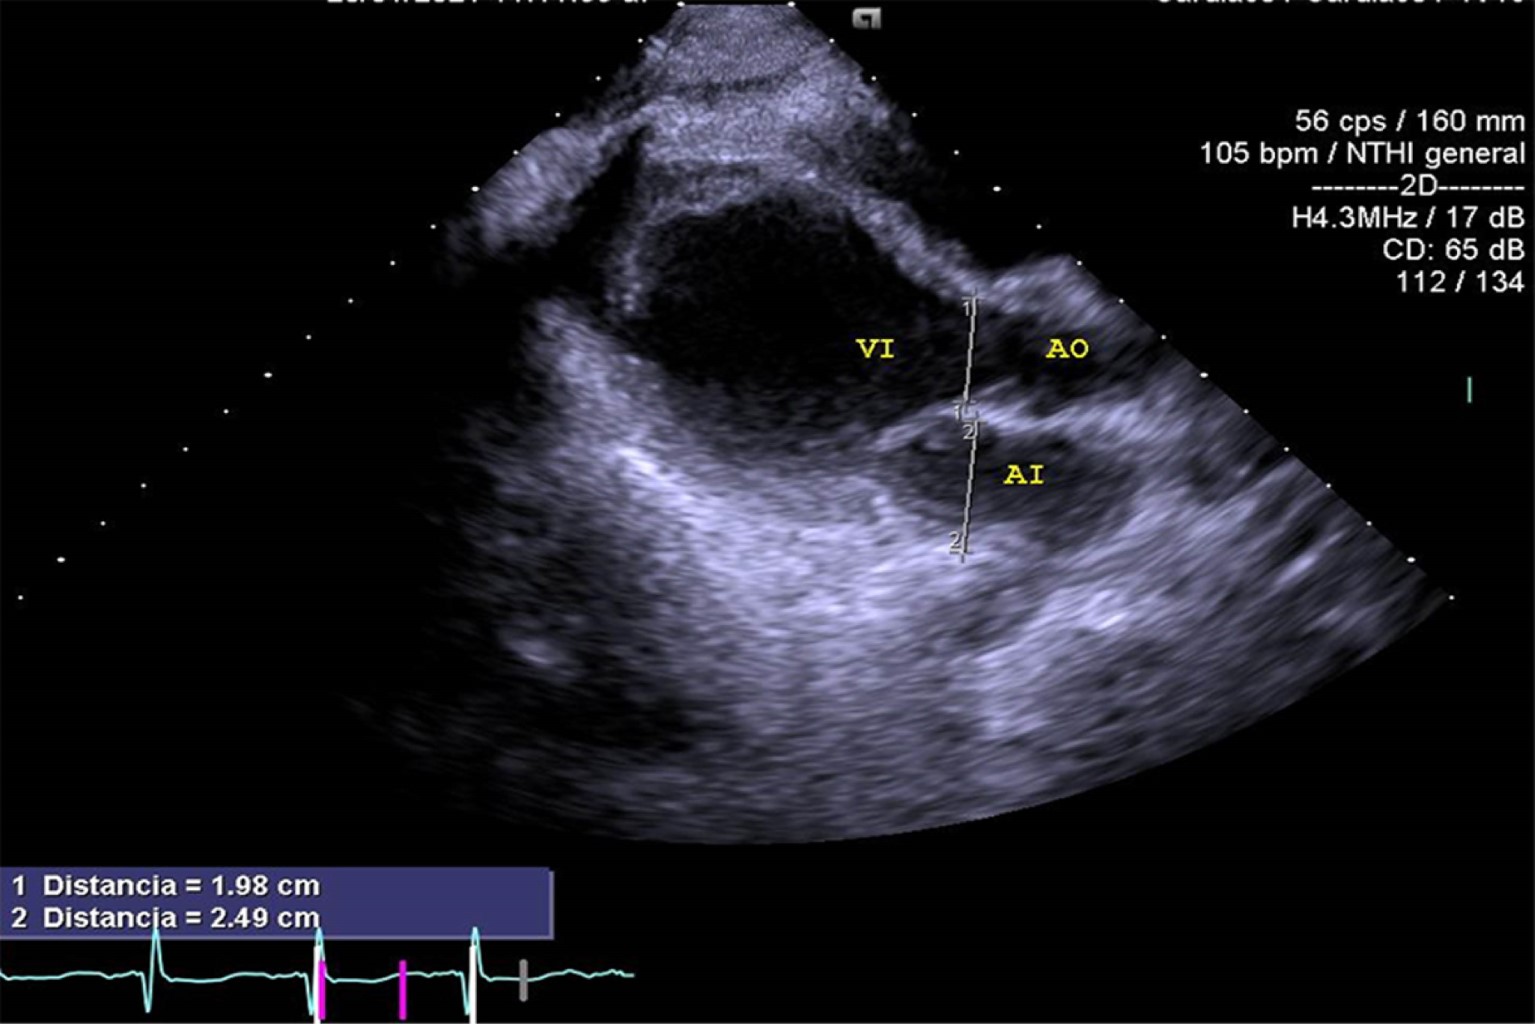

Mujer de 17 años de edad sin antecedentes de importancia, la cual ingresa al área de urgencias trasladada por paramédicos en camilla después de sufrir trauma debido a desaceleración súbita por caída de 10 metros de altura, sufriendo contusión directa y múltiples fracturas en miembros pélvicos, pelvis y cara, por lo que se le realizó colocación de fijadores externos en pelvis y lavado quirúrgico. Ingresó a terapia intensiva con Glasgow de 15 puntos, facies álgica, palidez de piel y tegumentos, con dolor intenso en pelvis escala visual analógica (EVA) 9/10. Con requerimiento de oxígeno suplementario a cinco litros por minuto con disminución de los movimientos de amplexión y amplexación del hemitórax derecho, matidez a la percusión, aumento de las vibraciones vocales y disminución de murmullo vesicular en región basal de hemitórax derecho; signos vitales: presión arterial (TA) 90/50 mmHg, frecuencia cardiaca (FC) 109 latidos por minuto (lpm), frecuencia respiratoria (FR) 16 respiraciones por minuto (rpm), saturación periférica de oxígeno (SpO2) 100%, temperatura 36.6°C, llenado capilar 4 s. Laboratorio: hemoglobina (Hb) 6.8 g/dL, hematocrito (Hct) 19.9%, plaquetas 88,000 × 109/L, tiempo de protrombina (TP) 17.3 s, tiempo parcial de tromboplastina (TPT) 27.5 s, índice internacional normalizado (INR) 1.29, creatina fosfocinasa (CPK) 1,282.52 U/L, isoenzima MB de la creatina cinasa (CPK-MB) 1.2 ng/dL. Se realiza tomografía de abdomen, la cual evidencia hematoma retroperitoneal evolutivo desde plano fascial y perirrenal posterior. La paciente ameritó ventilación mecánica y fue sometida a laparotomía exploradora de urgencia. A su egreso de quirófano y posterior a la reanimación con hemoderivados, continuó con datos de choque con TA 60/40 mmHg, frecuencia cardiaca 105 lpm, llenado capilar 5 s, por lo cual requirió manejo con doble vasopresor: norepinefrina 0.15 μg/kg/min y vasopresina 0.03 UI/h; sin embargo, continua con presión arterial media < 65 mmHg. Se le realiza radiografía de tórax (Figura 1) donde se observa contusión pulmonar en región basal de hemitórax derecho, con corazón en gota. Electrocardiograma (ECG) (Figura 2): ritmo sinusal, frecuencia cardiaca 120 lpm, con aplanamiento de la onda T en la mayoría de las derivaciones excepto en V2, depresión del segmento ST en aVR y ausencia de elevación del segmento ST en V1. Se realizó ecocardiograma transtorácico (ECOTT) (Figuras 3 y 4), en el que se observa movilidad conservada solamente en ápex, condicionando tracción del ventrículo derecho; resto con hipocinesia generalizada, ventrículo derecho dilatado con función sistólica global deprimida con hipocinesia generalizada, fracción de eyección del ventrículo izquierdo (FEVI) 21.7%, puntaje InterTAK de 49 puntos. Requirió manejo con inotrópico dobutamina 3 μg/kg/min con mejoría de presión arterial media y datos de choque. Presentó una evolución favorable, logrando retiro de inotrópico 24 horas después por mejoría con control ecocardiográfico seis días después (Figura 5), con recuperación de FEVI: 64.3%. La paciente requirió fijación de fracturas de huesos de la cara y miembros pélvicos y posteriormente fue trasladada a otra unidad hospitalaria para continuar con tratamiento ortopédico.

Figura 4